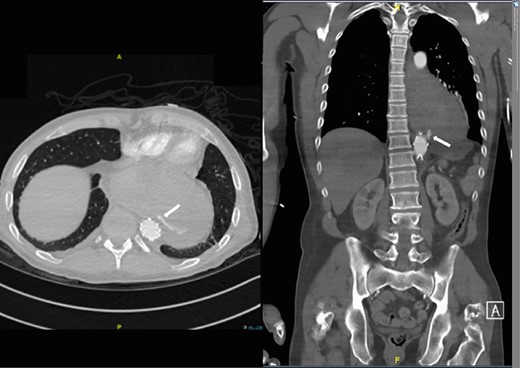

However, 4 and a half months later he again became haemodynamically unstable with a further episode of haematemesis. A further CT angiogram showed contrast entering the neo-oesophagus from the thoracic aorta (Fig. 5). The patient was again taken to the emergency theatre and the previous stent was relined with further stents extending both proximally and distally beyond the previous stent, with care taken not to occlude the celiac trunk and arteries below this (Cook Medical ZTA-26-105 and Cook Medical ZTA-28-109). Again, the patient had a quick recovery. However, repeat endoscopy showed that the aortic stent was visible through a defect in the wall of the neo-oesophagus (Fig. 6).

Second admission: CT angiogram showing aorta-enteric fistula demonstrated by arrow (axial and sagittal view, respectively).